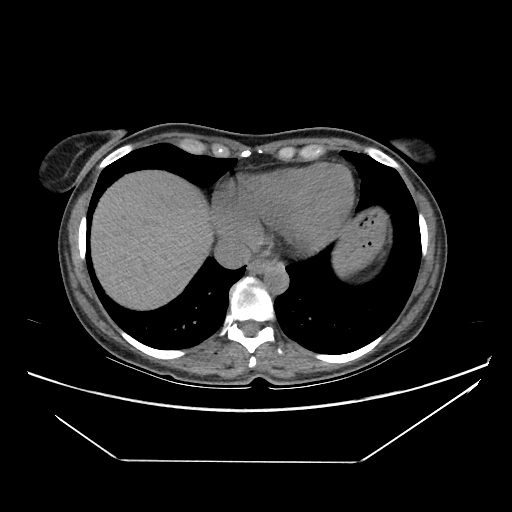

Original NATIVE CT scan (input)

No window - Raw intensity values

Original VENOUS CT scan

Generated VENOUS CT scan (A→B translation)